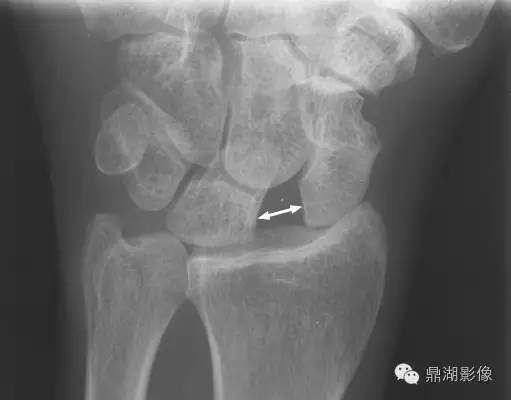

影像表现:当舟月骨分离、舟月骨间韧带撕裂所致腕关节正位片或CT冠状位示舟月骨间隙增宽,形似稀疏的牙缝。

(1)舟月骨间间隙>2mm为可疑分离,如>4mm即可诊断。